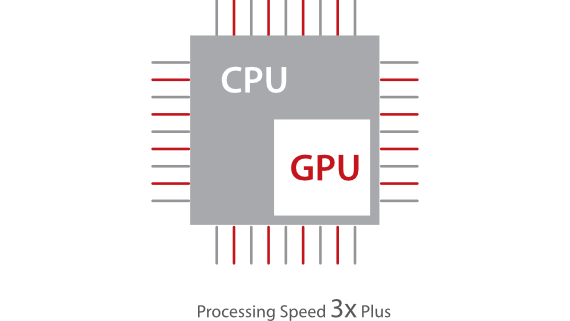

Sobre la base de un profundo conocimiento de las necesidades del cliente, el DC-60?ECHO con X-Insight estå dise?ado para brindar alta eficiencia con imågenes precisas, lo que se ve potenciado con eXpress Clarity (claridad exprés), eXceptional Intelligence (inteligencia excepcional) y eXceeding Experience (experiencia extraordinaria).